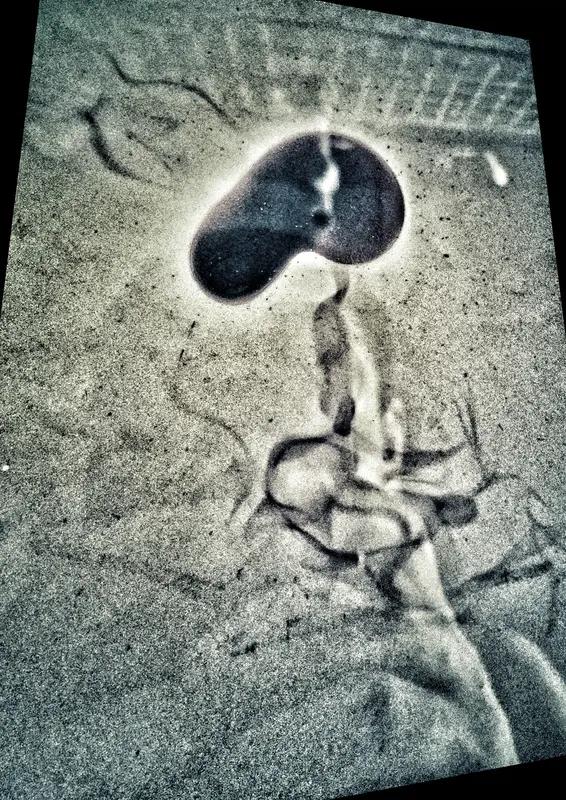

33岁男子频繁揉脖子后突发脑梗 脖子不舒服就揉一揉,这看似平常的举动,却可能暗藏巨大风险。武汉33岁的王先生,就因为频繁揉脖子吃了大亏。他在去机场途中头晕,习惯性用力揉捏脖子,到机场后就言语不清、肢体无力,最后失语偏瘫。 经检查,是椎动脉夹层导致大血管堵塞。医生说,夹层会激活凝血系统产生血栓。好在抢救及时,采用介入下动脉溶栓打通血管,王先生才转危为安。 原来,椎动脉血管夹层在年轻人中不少见,多和外力刺激有关。所以啊,颈部那些供应大脑的关键血管可不能随便按、扭、甩,颈肩不适还是赶紧去正规医院,别盲目按摩,不然像王先生这样就太危险了。